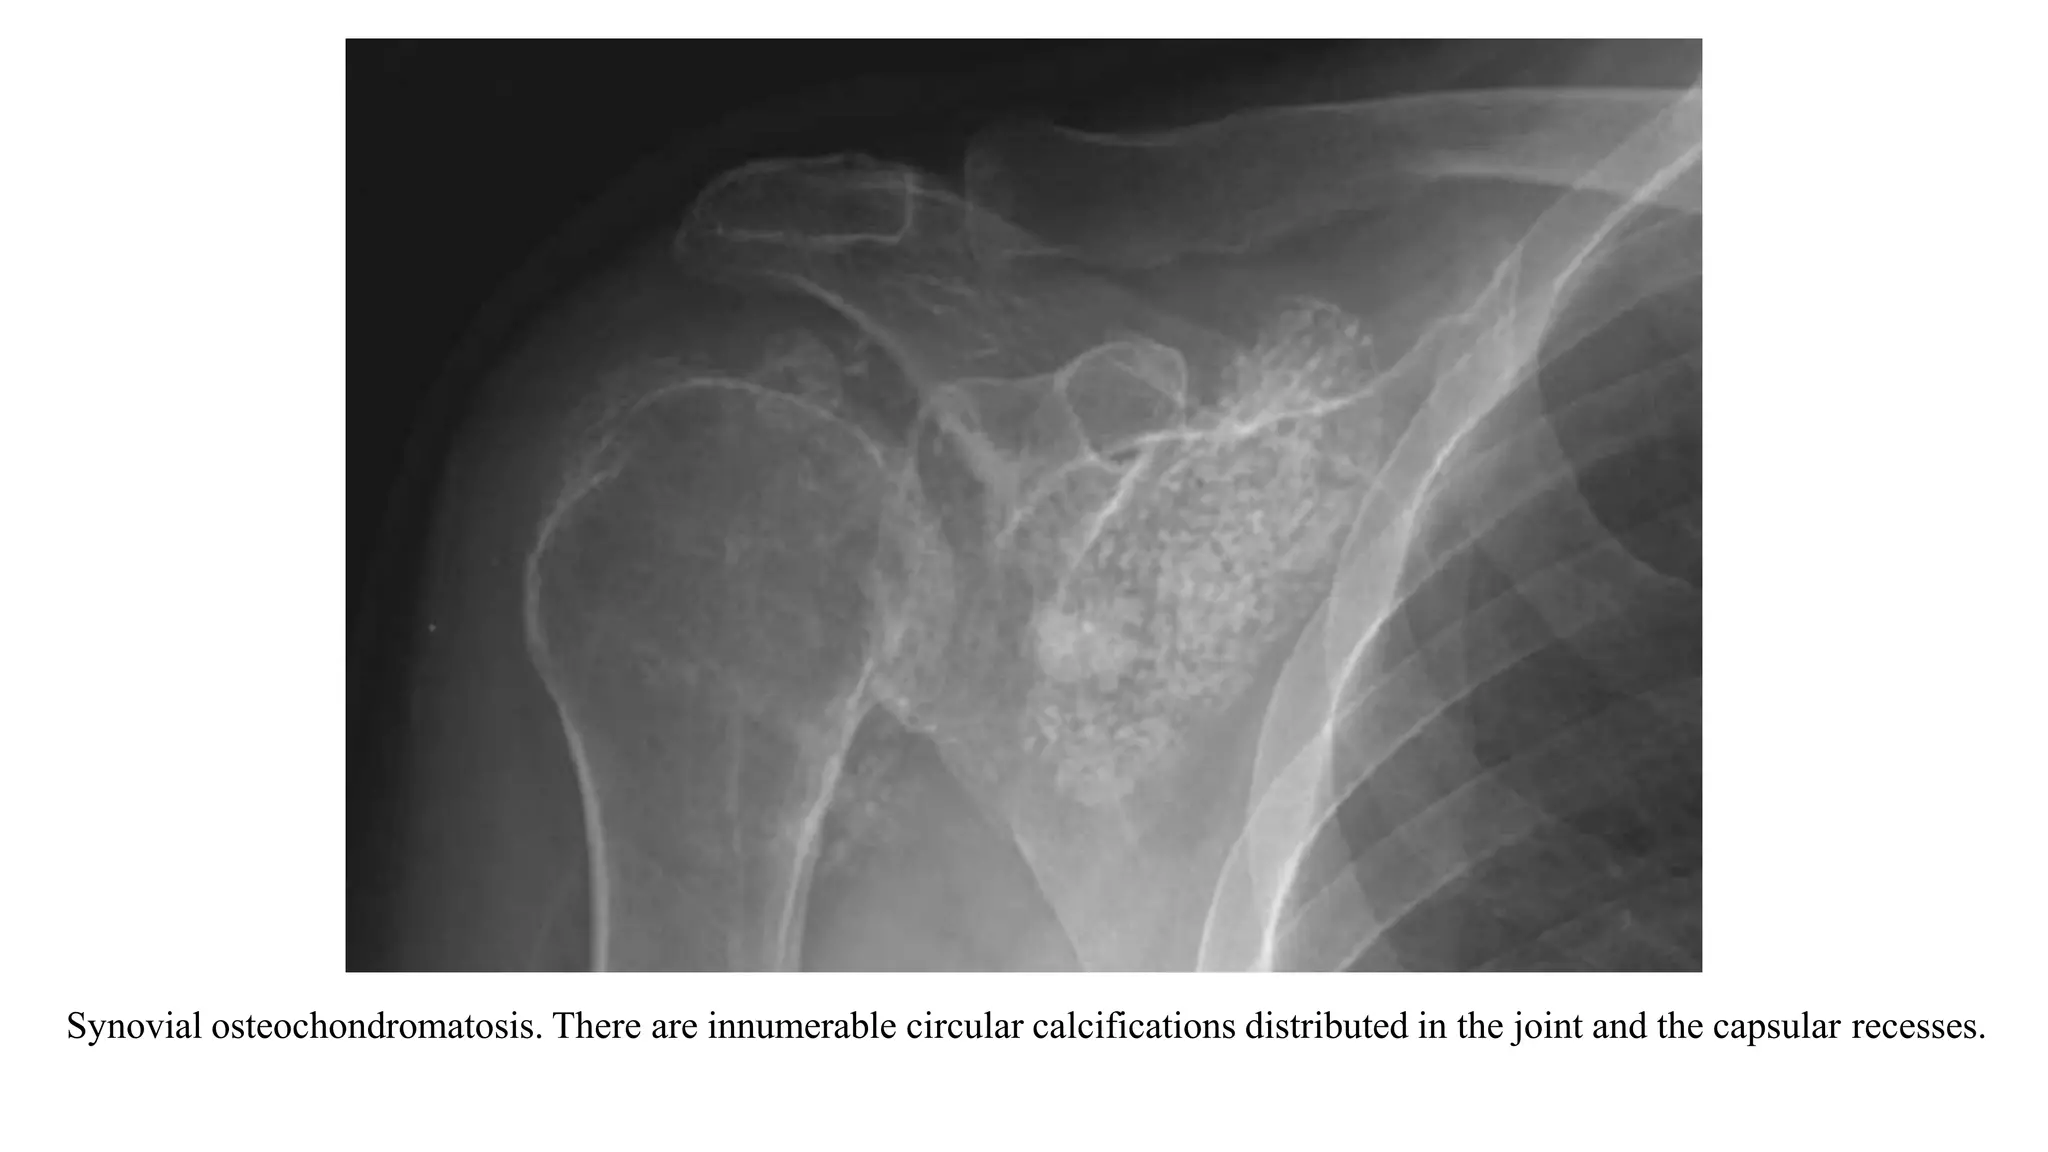

4. SYNOVIAL OSTEOCHONDROMATOSIS

• Primary synovial chondromatosis is a benign, predominately monoarticular disease.

• It results from synovial membrane proliferation and metaplasia forming multiple cartilaginous

nodules that may detach into the joint.

• As the chondroid fragments are bathed and nourished in the synovial fluid, they can enlarge and ossify.

• When the intra-articular chondroid fragments are not calcified or ossified, shoulder radiographs can

appear normal.

• As the fragments ossify, well defined circular opacities are seen within the joint or the bursae of the

shoulder

Synovial osteochondromatosis. There are innumerable circular calcifications distributed in the joint and the capsular recesses.